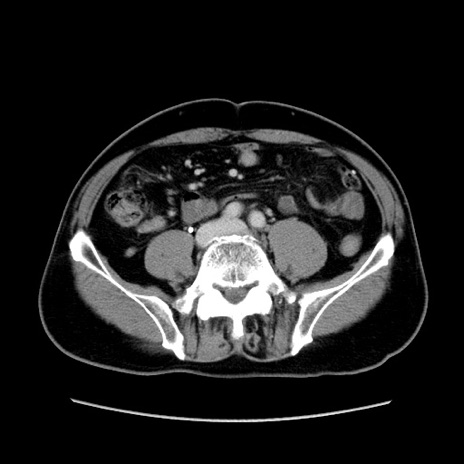

症例34(横断像)

【症例】60歳代 男性

【主訴】右鼠径部膨隆

【現病歴】1年程前より右鼠径部膨隆あり。自己にて還納可能だったため放置していた。3時間前より右鼠径部の脱出を認め、還納困難となり受診。

【身体所見】右鼠径部に小児頭大の膨隆あり。弾性硬であり、用手還納は困難。左鼠径部にも膨隆を認める。脱出はなし。